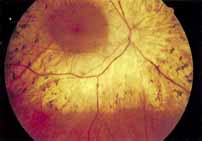

Although there is no reported genetic heterogeneity, there is wide phenotypic variation within the disorder. The major finding within the macula is a classic radial cystic maculopathy. Although retinal signs have been described in infants as young as 3 months, foveal schisis may be difficult to detect, leading to underdiagnosis. The diagnosis is usually not made until the affected male reaches school age (4 to 8 years of age) and encounters visual problems secondary to foveal involvement. Typical foveal schisis findings have been reported in 68% to 100% of eyes within various series.37,38 Foveal schisis is the only finding in about half the cases. It is characterized by the presence of radiate perifoveal microcysts located in the nerve fiber layer (Fig. 1) with radiate plications of the overlying internal limiting membrane that are seen especially well on monochromatic (red-free) photography (Fig. 2). The microcystoid change may slowly progress to form a macular cyst or hole. Foveal schisis has been reported in association with Goldmann-Favre vitreotapetoretinal dystrophy and rarely may be seen in rod-cone dystrophy or as an autosomal dominant or recessive condition.39–43